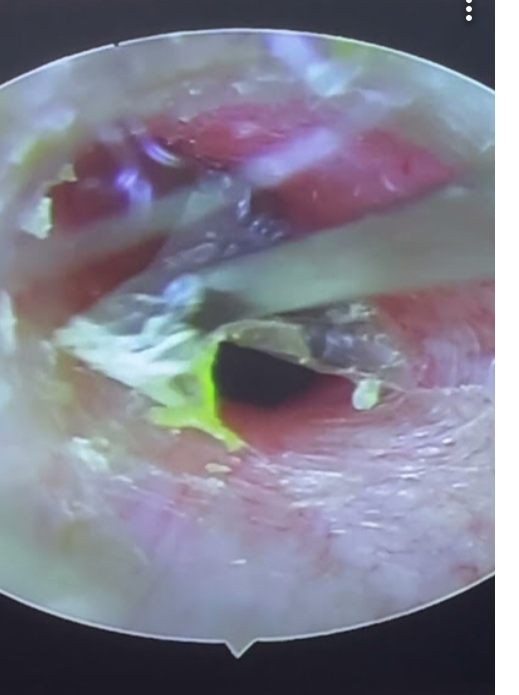

耳かき施術は体験しましたか?

当店ではイヤースコープを使いモニターでお客様が耳の中を確認しながら耳かきを致します。

まだ体験した事の無い方は是非お試し下さいね💕